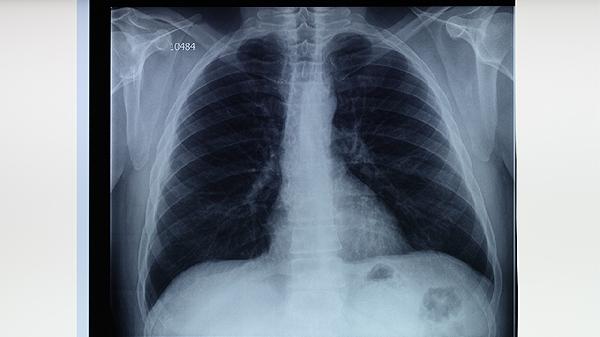

肺结核的治疗强调早期、联合、适量、规律和全程用药,患者必须在结核病专科医生指导下制定个性化方案。除了严格遵医嘱服药,患者在治疗期间应保证充足的营养,摄入富含优质蛋白和维生素的食物,如鸡蛋、牛奶、瘦肉和新鲜蔬菜水果,以支持身体修复。注意休息,避免劳累,居住环境应保持通风良好。定期复查痰菌、胸部影像学和肝肾功能至关重要,以便医生评估疗效和调整方案。完成全部疗程是治愈的关键,即使症状消失也不可擅自停药。保持良好的心态,积极配合治疗,绝大多数肺结核患者是可以治愈的。